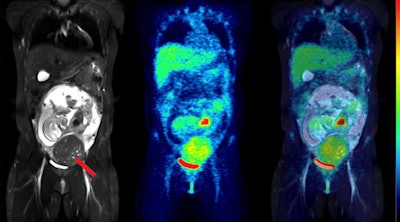

Coronal slices of MRI (left), PET (center), and fused PET/MRI (right) of the same woman as above, but at 24 weeks of pregnancy. The fetus has visibly increased in mass, but the pattern of F-18 FDG uptake in the organs has not changed, with the heart showing high glucose consumption but the brain still largely silent. The red arrow points to a uterine fibroid.This was the first such F-18 FDG dosing study in pregnant women to use imaging entirely acquired with PET/MRI, which allowed detailed visualization of the fetal body contours, they noted. Hence, dose estimations were arguably more accurate than in previous reports, according to the group.

Moreover, such accuracy cannot be achieved by coregistering the PET image to an MRI acquired separately because the fetus would have moved in the meantime.